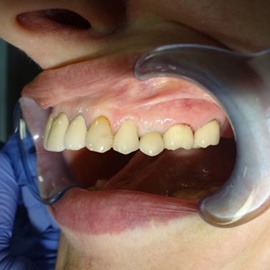

Odbudowa lewego dolnego trzonowca.

Odbudowa prawego dolnego trzonowca.

Uzupełnienie trzonowców: szóstki i siódemki na implantach.

Odbudowa kości, dziąsła, implantacja, korony protetyczne, dwa prawe dolne trzonowce.